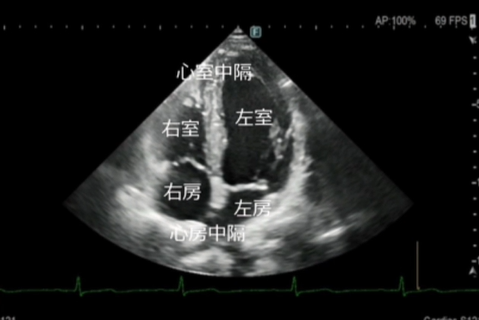

当院では、短時間・低負担での撮影が可能なCTや、放射線を使用しないオープンMRIを利用し、必要に応じて隣接医療機関の高度な検査機器も共同で使用しています。 - 超音波検査(エコー)

お腹の臓器、心臓、血管などを、体に負担をかけずにリアルタイムで観察します。

しこりや腫瘍、血流の状態なども調べることができます。 - 血圧脈波検査(CAVI検査)

心エコー検査は、超音波を用いて心臓の形や動き、血流の流れを詳しく観察する検査です。

放射線を使用しないため、身体への負担が少なく、安全に繰り返し行うことができます。

超音波診断装置

当院の超音波診断装置(エコー装置)は、高画質で多彩なプローブバラエティと臨床アプリケーションにより、腹部・表在・循環器などの幅広い分野での検査が行えます。当製品はPrecision Imagingを搭載し、超音波画像を形成する信号を処理することにより、組織信号を強調し、生体内組織の境界などの構造視認性を高め、腫瘍部分などがより描出しやすくなっております。

エコー(心臓超音波)検査

- このようなことが分かります

弁膜症の評価

心臓の弁(大動脈弁・僧帽弁など)の開き具合や逆流の有無を確認します。

弁の狭窄や逆流の程度を評価し、治療方針の判断に役立てます。 - 心筋の働き(ポンプ機能)の評価

心臓がどのくらいしっかり血液を送り出せているか(収縮機能)を確認します。

心筋梗塞後の機能低下や、拡張型心筋症などの診断にも重要です。 - 心不全の原因検索

息切れやむくみなどの心不全が疑われる場合、その原因が弁膜症によるものか、心筋の

弱りによるものかを詳しく調べます。 - その他

心肥大の有無・心臓内血栓の確認・先天性心疾患の評価・肺高血圧症の推定 など - 検査について

検査時間はおおよそ20~30分程度です。

ベットに横になっていただき、胸にゼリーを塗ってプローブ(探触子)を当て観察します。痛みはありません。

当院では、循環器疾患の早期発見と適切な治療につなげるため、症状がある方は、もちろん、健診等で指摘された方にも心エコー検査を行っております。

お気軽にご相談ください。